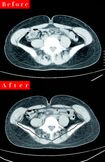

内臓脂肪を減らして痩せる身体をつくる!

脂肪肝とは中性脂肪が肝臓にたまった状態のことで内臓脂肪の一種。放置しておくと肝硬変や生活習慣病になるおそれがある。実は脂肪肝は近年、お酒を飲まない人や若い女性にも急増している。その多くは食べすぎや、甘いもののとりすぎが原因だ。

また、脂肪が増えれば内臓の働きも悪くなり、基礎代謝も低下する。齋藤先生もだんだん代謝が落ち、量は食べていないのに体重は増えていた。